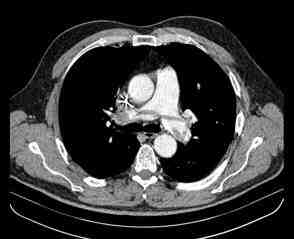

Figura 1. TAC abdomen: lesión ocupante de espacio (LOE) hepática de 7 cm en segmento VI-VII hepático

Figura 3. TAC tórax: defecto de repleción en tronco de arteria pulmonar